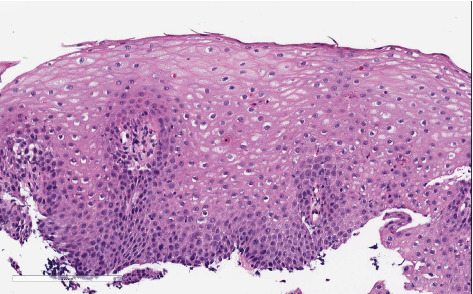

嗜酸性粒细胞性食管炎(EoE)是一种慢性免疫介导的疾病,以吞咽困难、食物嵌堵和食管嗜酸性粒细胞增多为特征,可导致纤维化和狭窄的形成。虽然纤维狭窄并发症在儿童中相对罕见,但研究表明,高达86%的成人EoE患者出现吞咽困难和食管狭窄,而儿童只有6%。此外,儿童狭窄形成的发生率仍然很低,报道的发生率约为3.4%。先前记录的患有这种并发症的最小的孩子是3岁。EoE患者纤维狭窄的危险因素包括年龄较大、病程延长和症状频率增加。这是已知的此类病例中最年轻的一例,表明纤维狭窄可能是该疾病的一种独特表型,而不仅仅是炎症形式的进展。考虑到早期狭窄发展的可能性,该病例强调了早期和彻底评估EoE的重要性。

Eosinophilic esophagitis (EoE) is a chronic, immune-mediated disorder characterized by dysphagia, food impactions, and esophageal eosinophilia, which can lead to fibrosis and the formation of strictures. While fibrostenotic complications are relatively rare in children, studies have shown that up to 86% of adults with EoE experience dysphagia and esophageal narrowing, compared to only 6% in children. Furthermore, the incidence of stricture formation in children remains low, with reported rates of approximately 3.4%. The youngest child previously documented with this complication was 3 years old. Risk factors for fibrostenosis in EoE include older age, prolonged disease duration, and increased symptom frequency. This represents the youngest known presentation of such a case and suggests that fibrostenosis may be a distinct phenotype of the disease, rather than merely a progression from the inflammatory form. This case underscores the importance of early and thorough evaluation of EoE, given the potential for early stricture development.